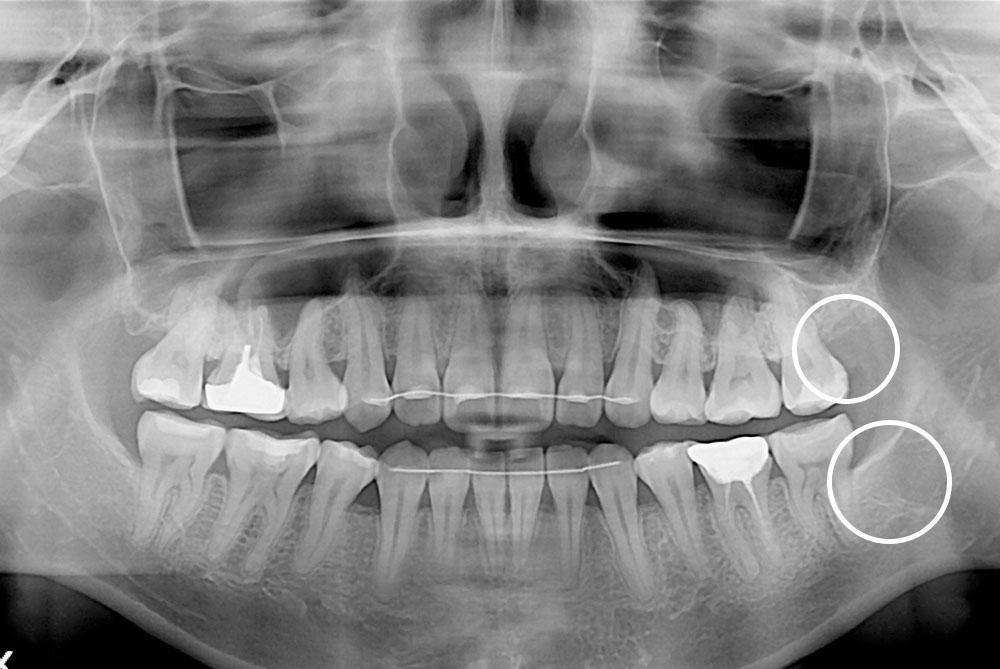

[사랑니] 매복 사랑니 발치

치료후 : 2021-04-28

세종치과는 구강악안면외과학 박사이신 원장님이 발치하는 치과입니다.